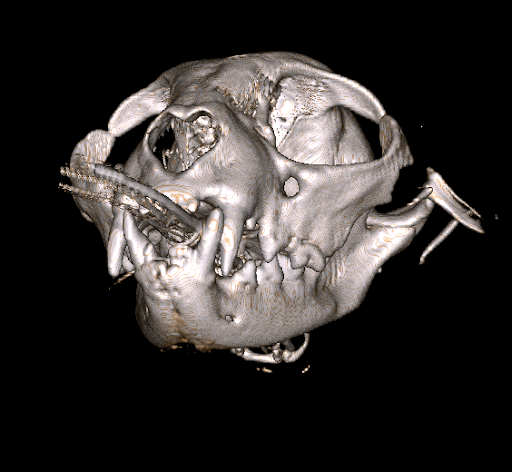

Figure 3. Three-dimensional reconstruction from cone computed tomography scan of a cat with a fracture of its zygoma bone. The fracture was the result of being attacked by a dog. The CBCT scan was completed at Animal Dental Care and Oral Surgery in Colorado Springs.